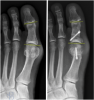

How To Repair An Overcorrected Akin

As with any osteotomy, the Akin osteotomy can also be subject to overcorrection. An overcorrected Akin does not produce a hallux varus per se. Rather, it produces a toe with an adducted tip. The hallux toenail will generally dictate an overcorrection and one often identifies it intraoperatively, although it can become more pronounced postoperatively. It is best to address overcorrection sooner than later. As the Akin osteotomy tends to be a closing wedge procedure, correcting the overcorrection often involves adding bone graft to create an opening wedge. If the surgeon identifies this during the index operation, he or she can replace the initial bone from the wedge or a portion of it back into the osteotomy. In the subacute stage, before the osteotomy has healed, one can still add bone graft but the source is either cadaveric or autogenous. Healed malunions require a new osteotomy and, depending on the clinical scenario, can be a medial opening wedge or lateral closing wedge. The fixation for revision Akin procedures depends on the correction that the surgeon is trying to achieve and whether one has added bone graft. In my experience, plate fixation occurs most often for the revision Akin because there is previous hardware that one is removing and this limits the availability for new hardware. Of course, the specific clinical scenario dictates the hardware choice. Locking plates may provide additional stability and a “T” or “L” plate configuration can fit a variety of osteotomies.